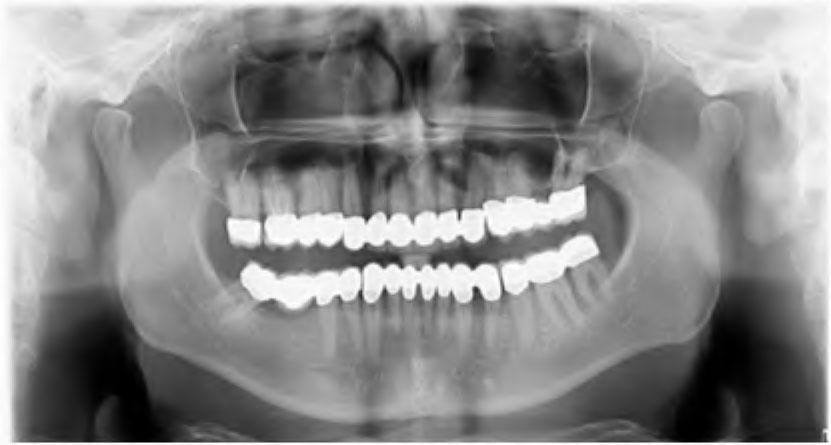

Intraoral and radiograph examination verified that 26 and 46 were missing and the endodontic treatment of 16 was no adequately performed. Caries lesions were found on the mesial surfaces of 11, 21 and 12. There was no pocket depth of over 2 mm or mobility around any of the remaining teeth. Panoramic radiograph confirmed that all the maxillary and mandibular teeth had favorable crown/root ratio of 2:3 (Figure 2). The patient’s oral hygiene was good.

Panoramic radiograph before treatment